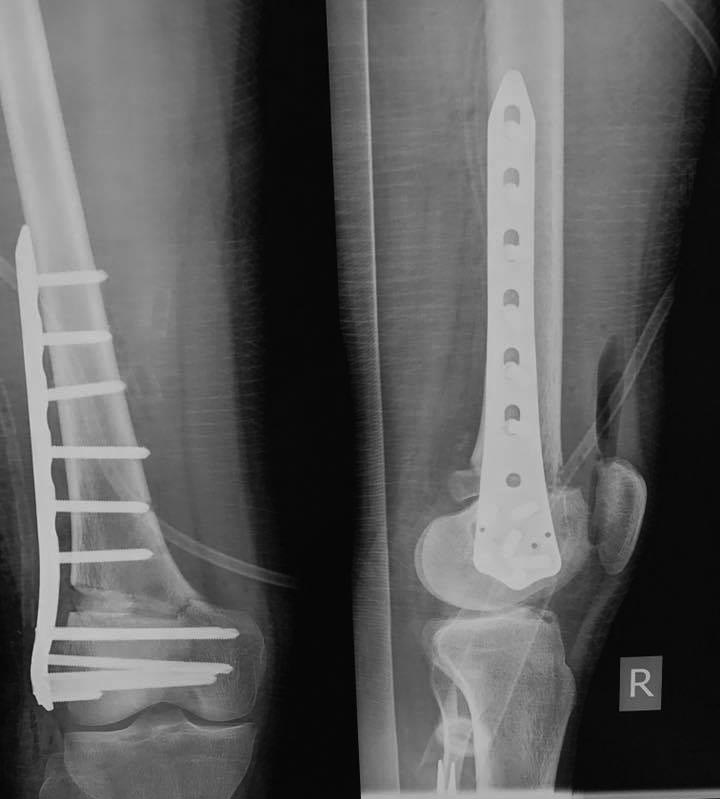

Re: Несращение бедра

Зачастую после удаления Штифта мы ставим подобную пластину. А протез можно и после сращения поставить.